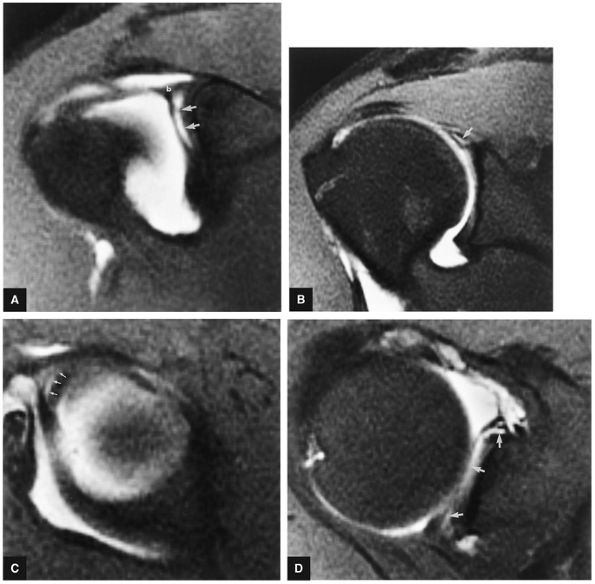

The SLAC lesion is combined with the anterior component of a SLAP 2 tear.

-

The SLAC lesion is a type of instability and not an impingement lesion.

![]() |

|

FIGURE 8.178 ● Potential sites of involvement in microinstability, including the anterior supraspinatus and anterior component of a SLAP 2 in the SLAC lesion; the posterior cuff and posterior component of a SLAP 2 in the posterior peel-back lesion; the classic anterior-to-posterior SLAP 2 lesion; anterosuperior impingement (ASI) involving the superior subscapularis, CHL–SGHL complex, the anterior supraspinatus and anterosuperior labrum, and the middle glenohumeral ligament (MGL) in anterior laxity.